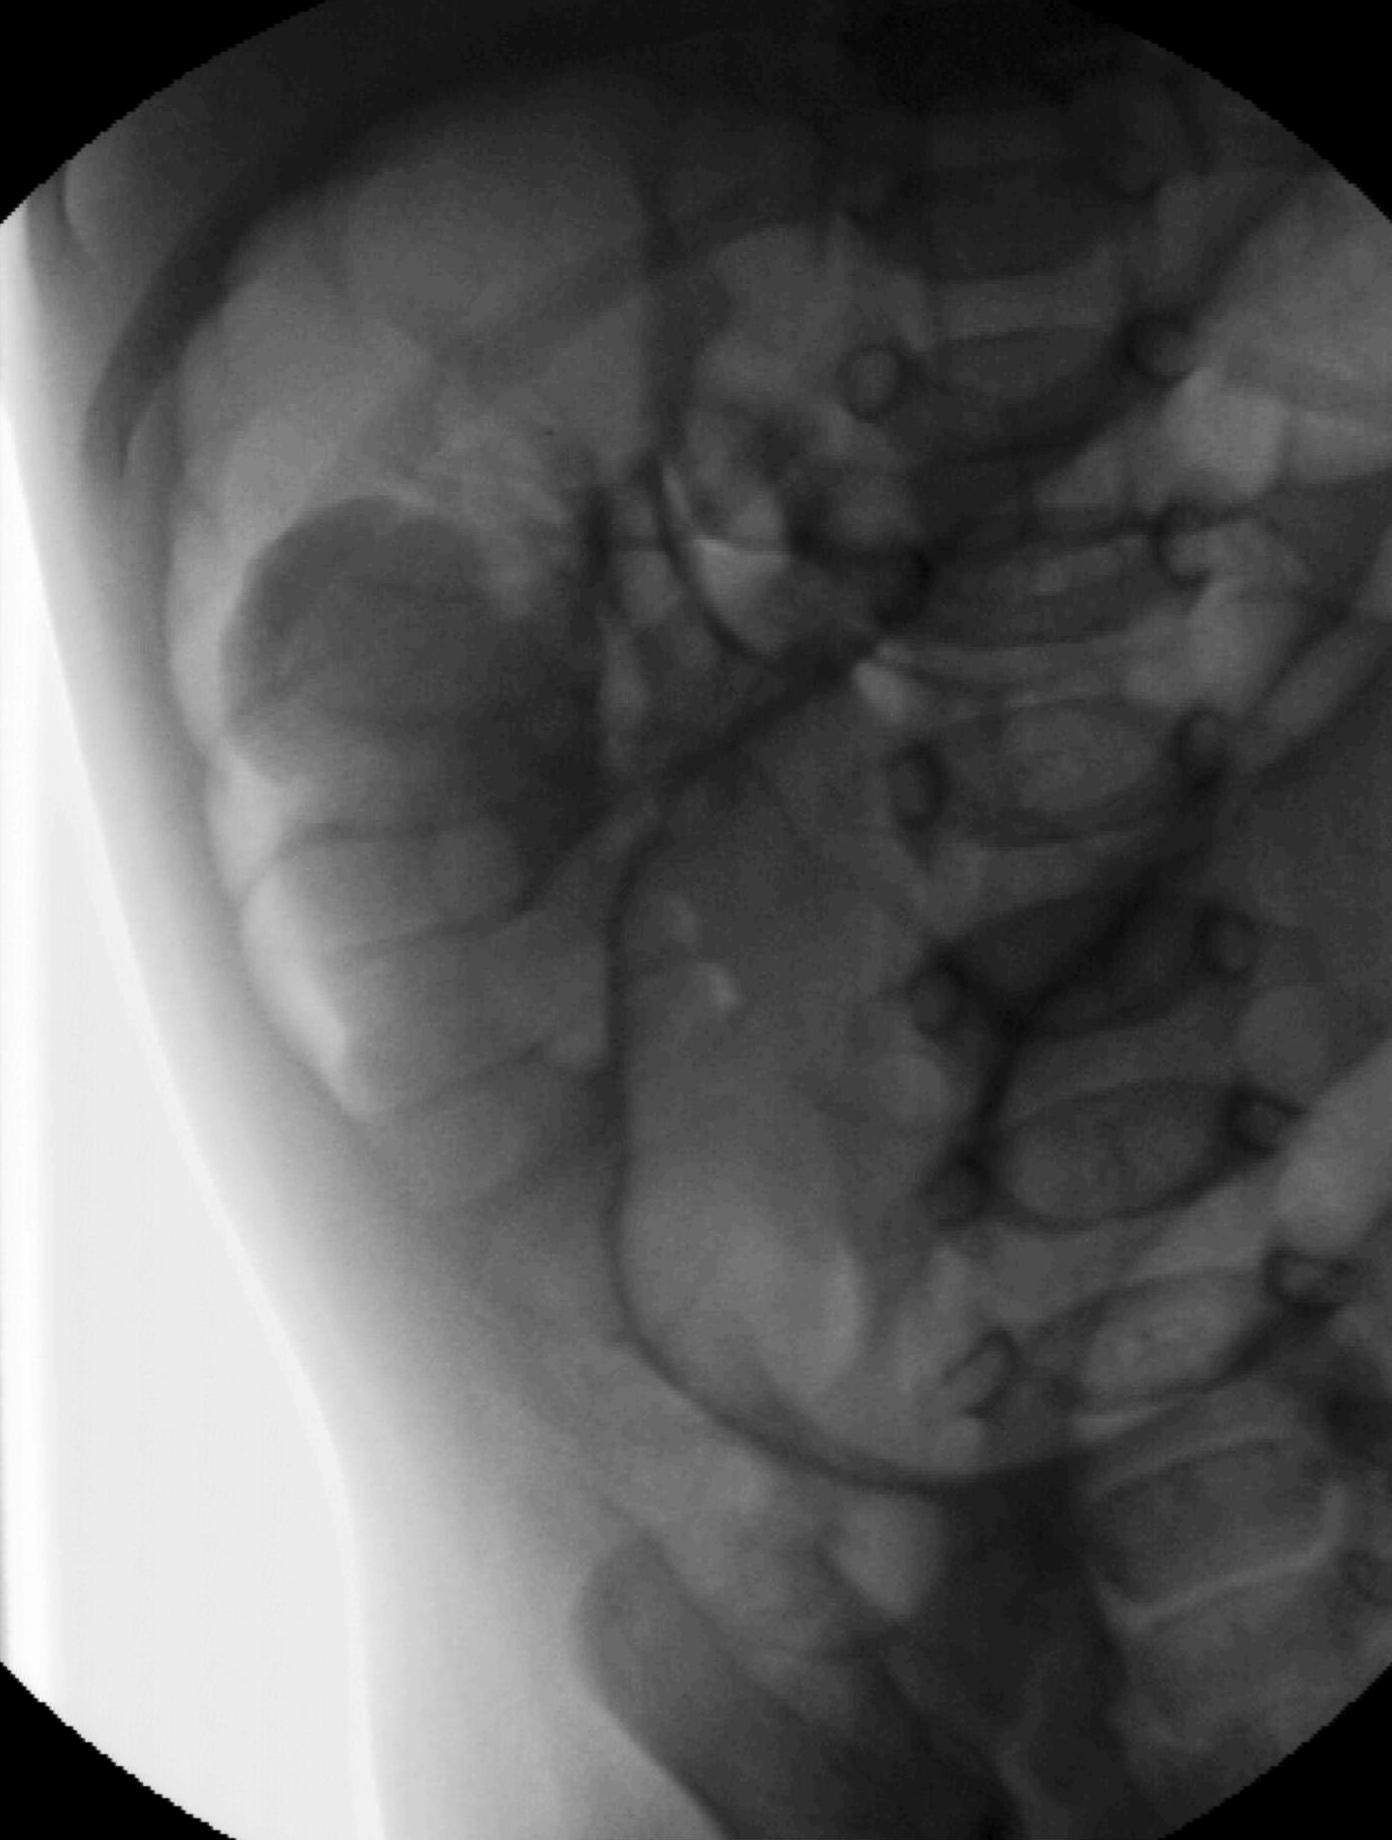

Invagination. A distal intestinal loop invaginating to a proximal intestinal loop can result in a mechanical intestinal obstruction, and cause ischemic damage. It most frequently occurs in infants (3-24 months) with recurring, colic-like complaints, distended intestines, a palpable mass and with frequent vomiting and bloody stool. Invagination requires immediate diagnosis and desinvagination. US exam reveals the invaginated intestines as a “target” sign in axial cross section and looks like a “pseudokidney” in longitudinal cross section. The therapy is hydrostatic or pneumatic desinvagination. Perforation and/or peritonitis are absolute contraindications to these procedures. Hydrostatic desinvagination can be performed under fluoroscopy or with US guidance and is considered successful if air or the contrast material appears in the terminal ileum and the invaginated loop disappears. If these efforts do not succeed, surgical desinvagination is needed.

Image

17. “Target” sign. Invagination. .

18.a-b-c-Desinvagination with air.

18. b. Arrow: invaginated segment.

18. c. Successful desinvagination